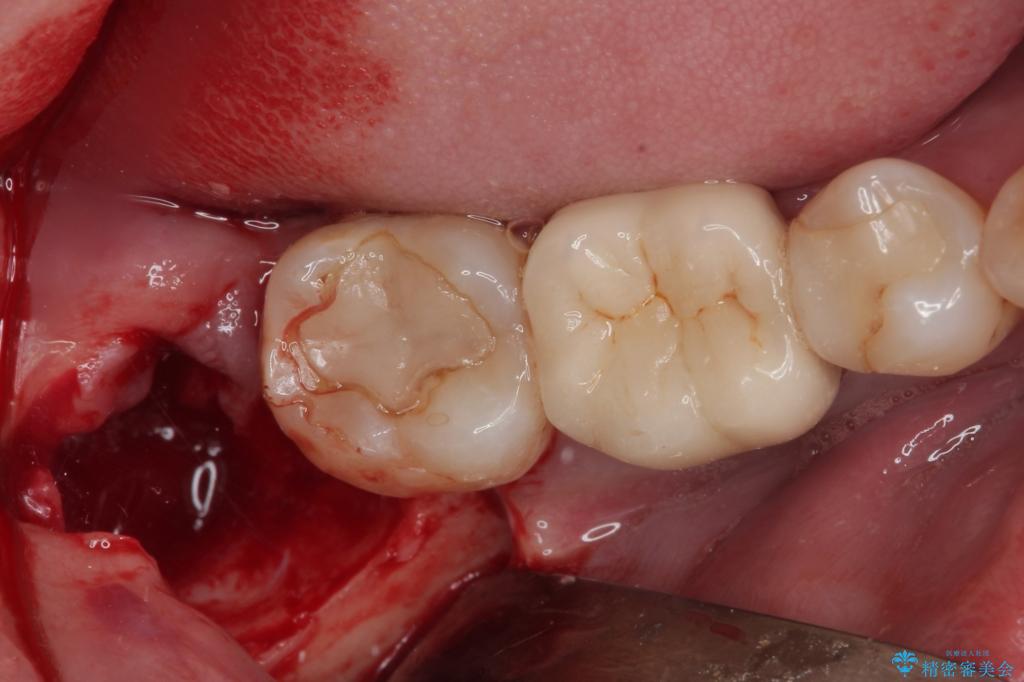

- 右下の親知らずを抜きたいとのことで来院された患者様です。

CTで神経の位置などを確認し、抜歯術を行いました。

一週間後に抜糸を行いました。

しっかり麻酔が効いたことを確認してから安全に抜歯を行いました。